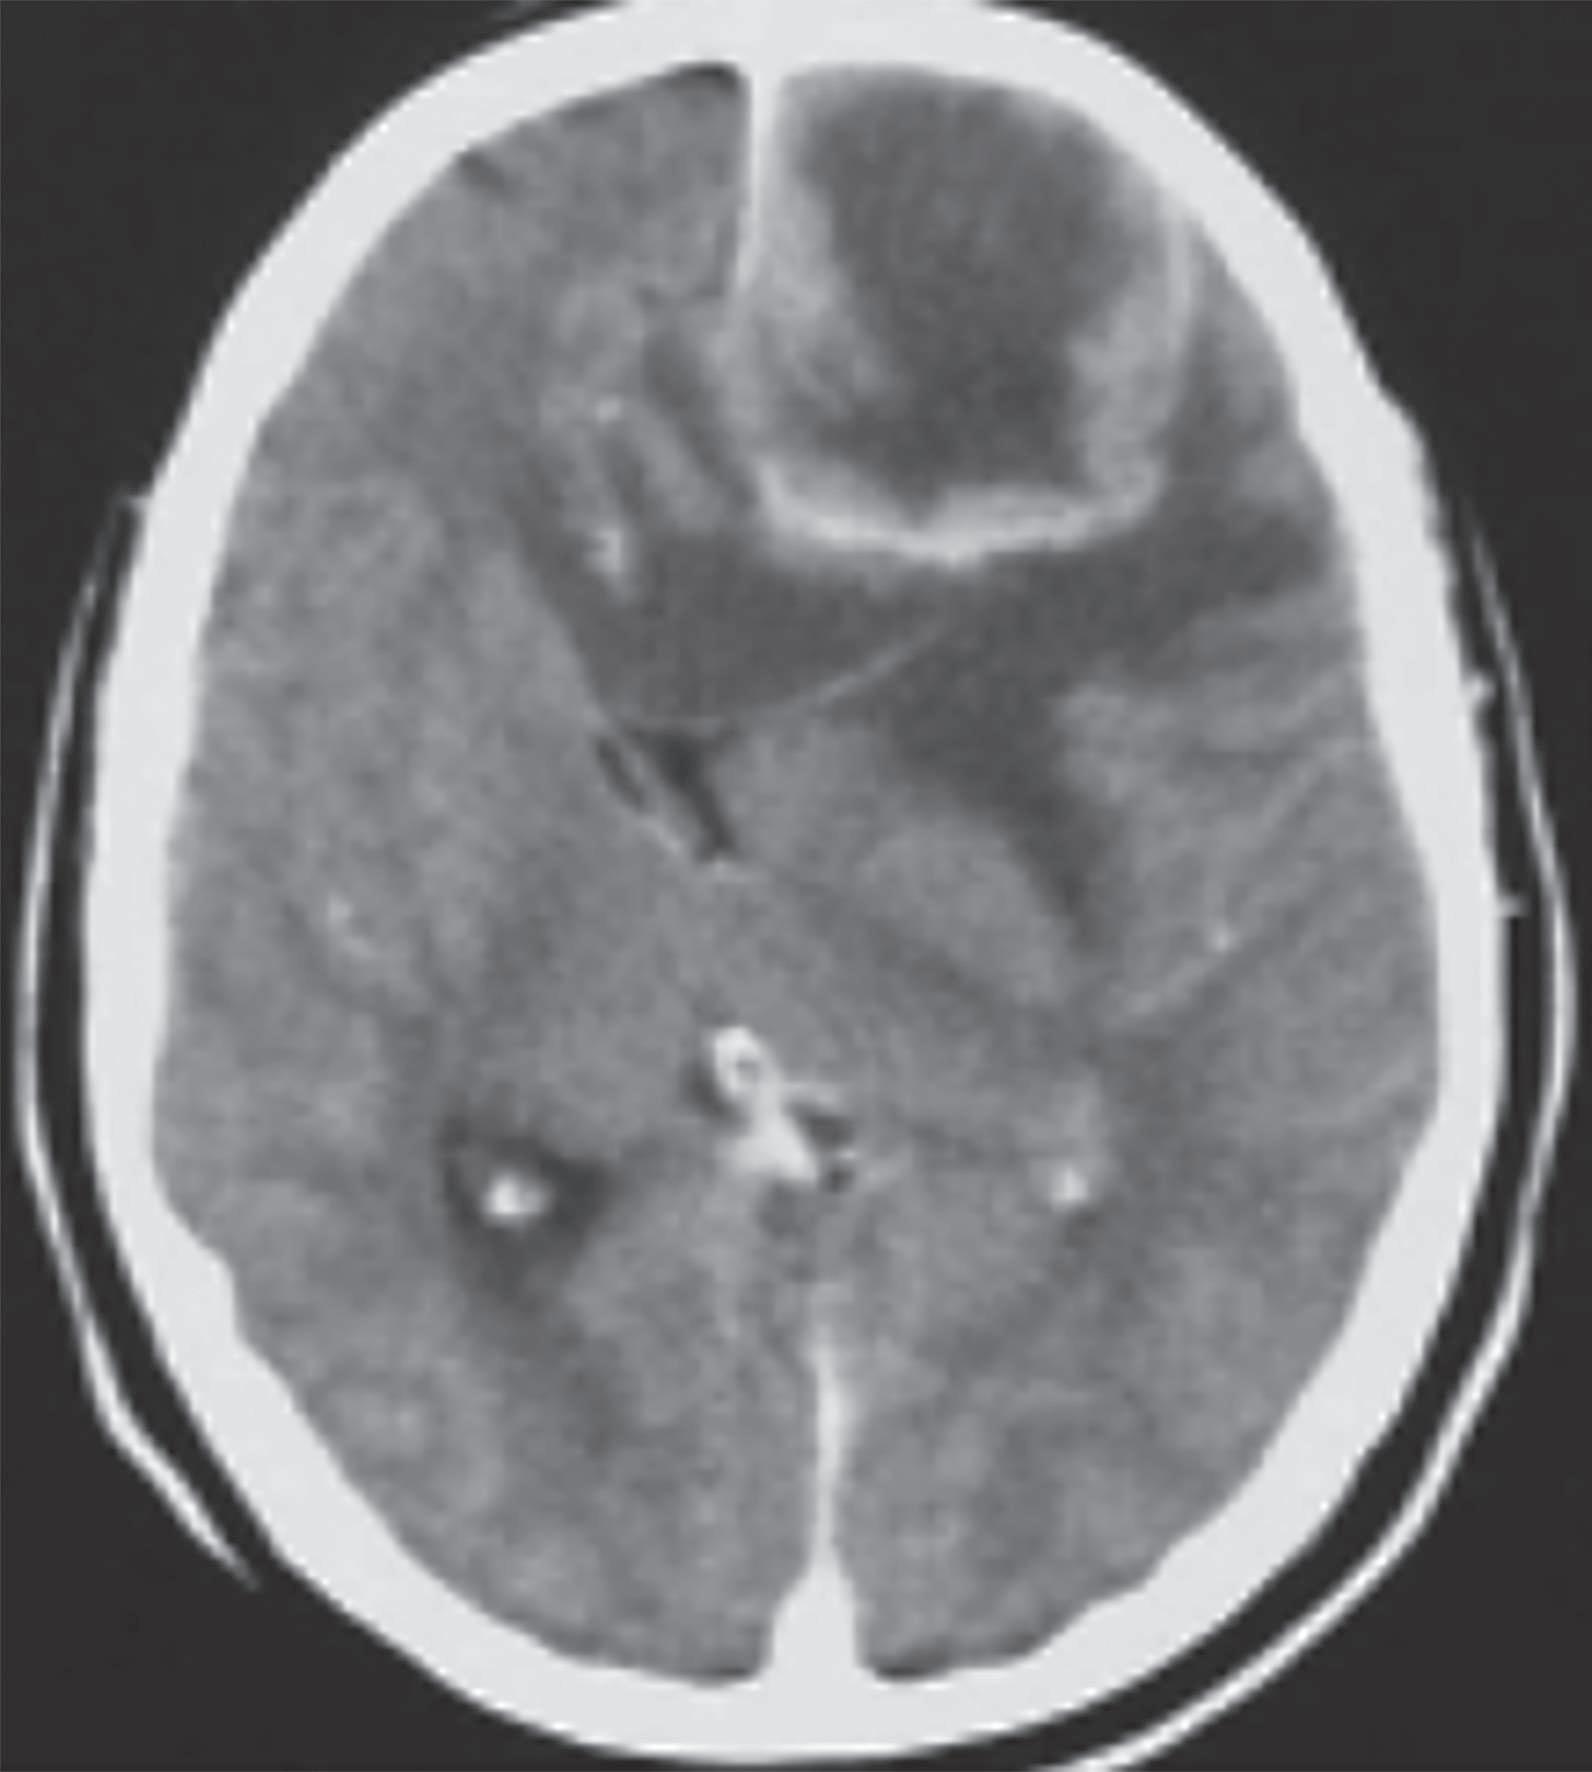

Figura 13.3 – Glioblastoma, grau 4 da OMS. A. TC revelando tumor frontal de aspeto heterogéneo com área de necrose central, marcado edema e efeito de massa com acentuado desvio da linha média. B. RM T1 mostra glioblastoma dos núcleos da base. É evidente a captação de contraste à periferia e a zona mais central não captante, correspondendo a necrose.